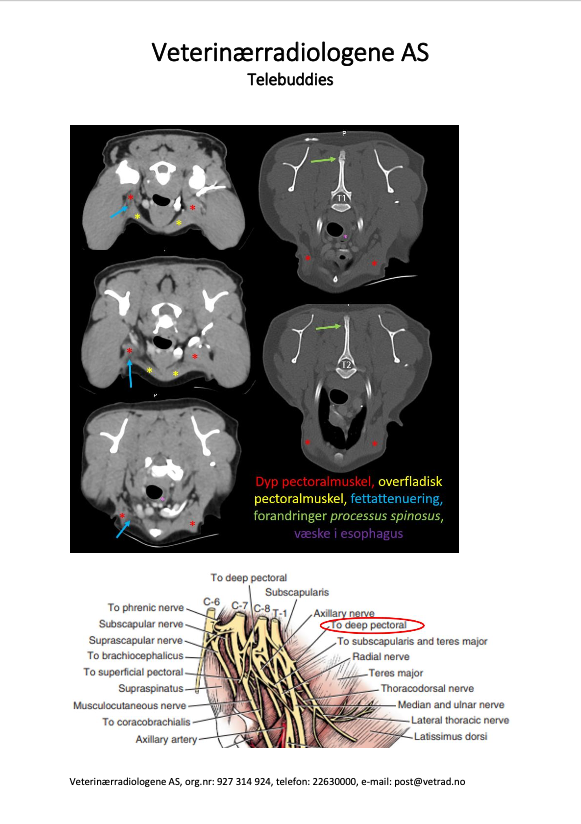

Denne godbiten har vi hatt på lager en liten stund, men vi har (heldigvis) hatt det travelt de siste ukene. Nå kommer endelig vårt nye kasus og vi vil gjerne benytte muligheten til å dele en fasinerende CT-studie som vi fikk inn fra Grong Dyreklinikk. Signalement: Blandingshund, hann, 8 år. Anamnese: Påkjørt for ca 5 år siden. Vondt høyre frambein og ble behandlet for fraktur i klobein. Hunden ble bedre, men så begynte han å halte på høyre frambein igjen. Klinisk mistenkes nerveskade.